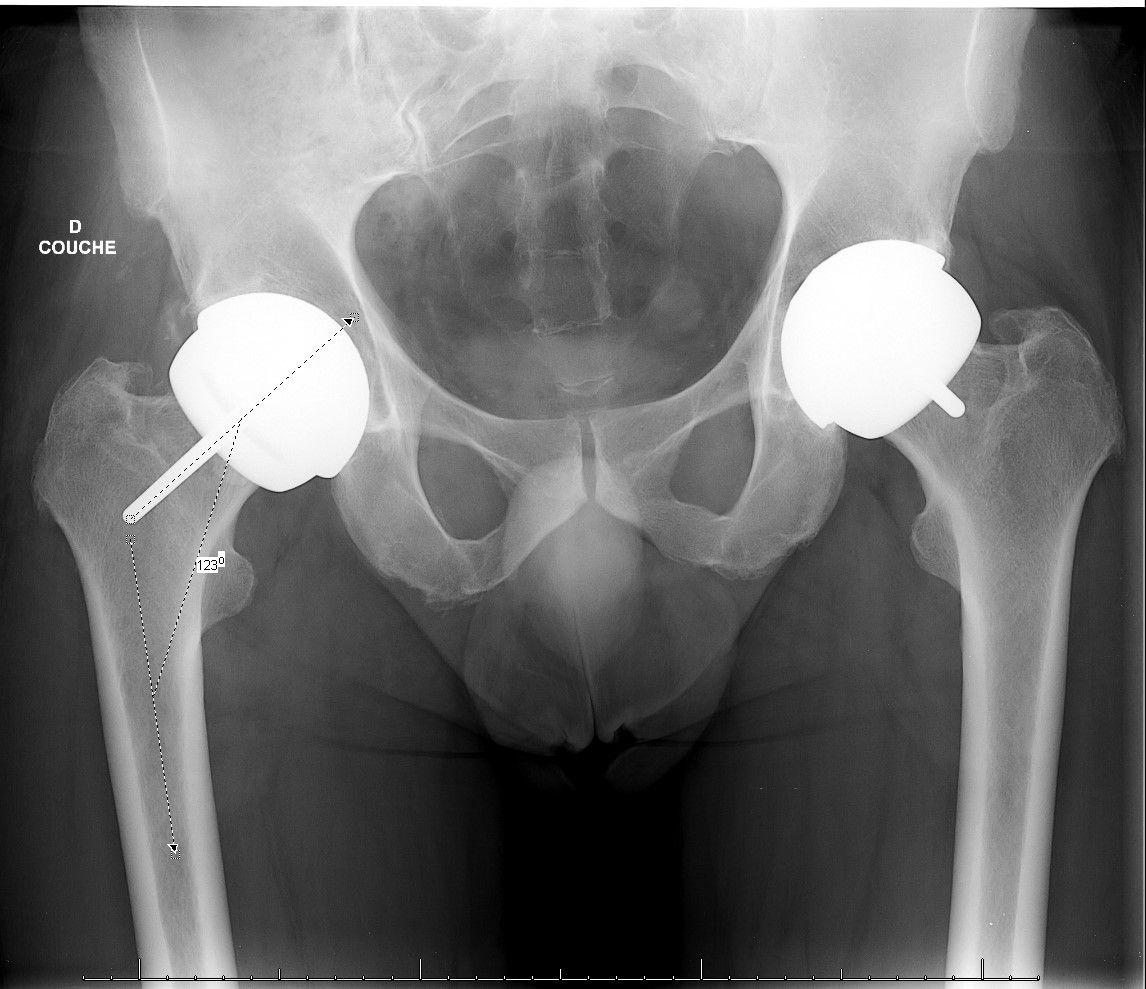

The accompanying articles address advanced reconstruction and emerging technologies across hip and knee surgery. The prosthetic management of coxa vara hips with increased femoral offset and planning and repair of acetabular defects in revision total hip arthroplasty examine solutions to complex anatomical challenges. Attention then shifts to the knee, covering patient-specific alignment and balancing with computer-assisted surgery in total knee arthroplasty and temporary arthrodesis using coupled AO rods. A dedicated contribution further evaluates the clinical integration of mixed reality and artificial intelligence in surgical practice.